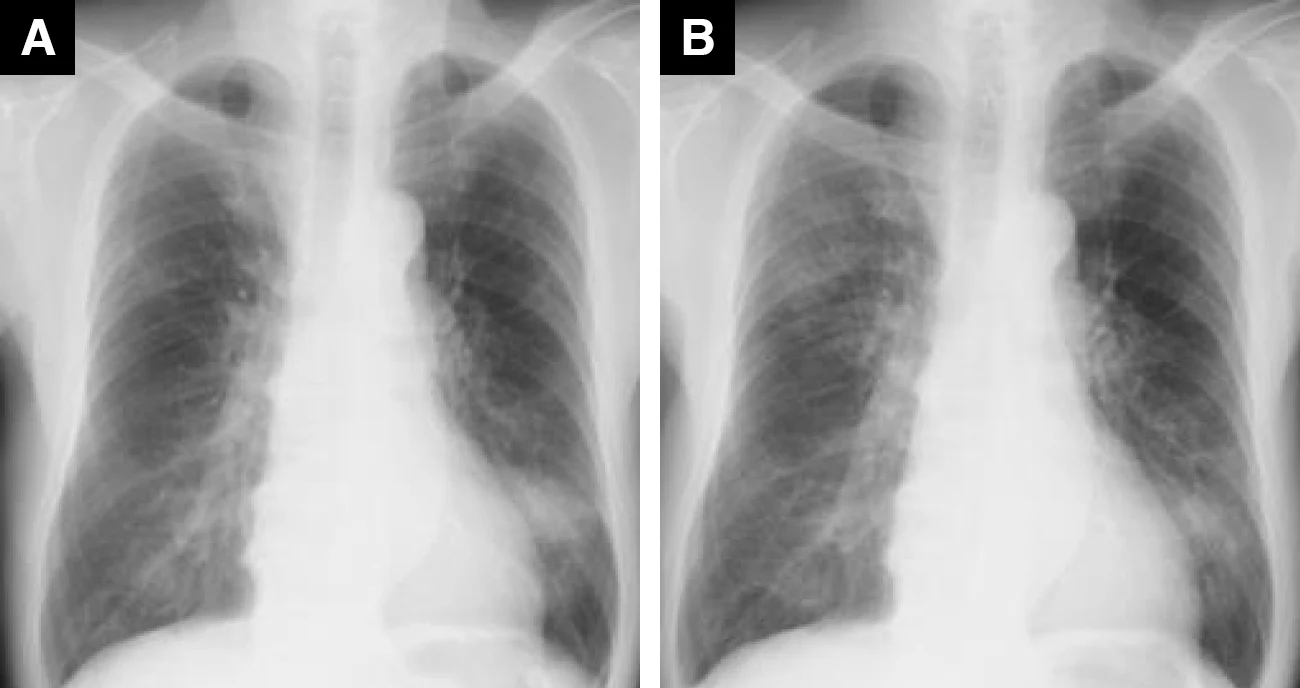

ドセタキセル投与症例(63歳、男性、乳がん)

A : 薬剤投与前 B : 薬剤投与後(紹介時)

Bでは極めて軽微ではあるが、両肺にすりガラス影を認めた